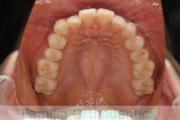

No.22V-498

- 上顎前突

- 側方偏位

- 26歳

- 女性

- 上:

- 44

- 下:

- 8|58

- FEA

- 90万円

上の前歯が出ているのと下の前歯のでこぼこを治したいということで来院されました。左右のズレがあるので、上顎を左右から、下顎は左下のみ小臼歯を抜歯して、アンカースクリューを併用したマルチブラケット法にて治療を行いました。2年強、25回程度の通院が必要でした。

前歯の移動量が多いケースとなりますので、歯根吸収や歯肉退縮のリスクが高めです。